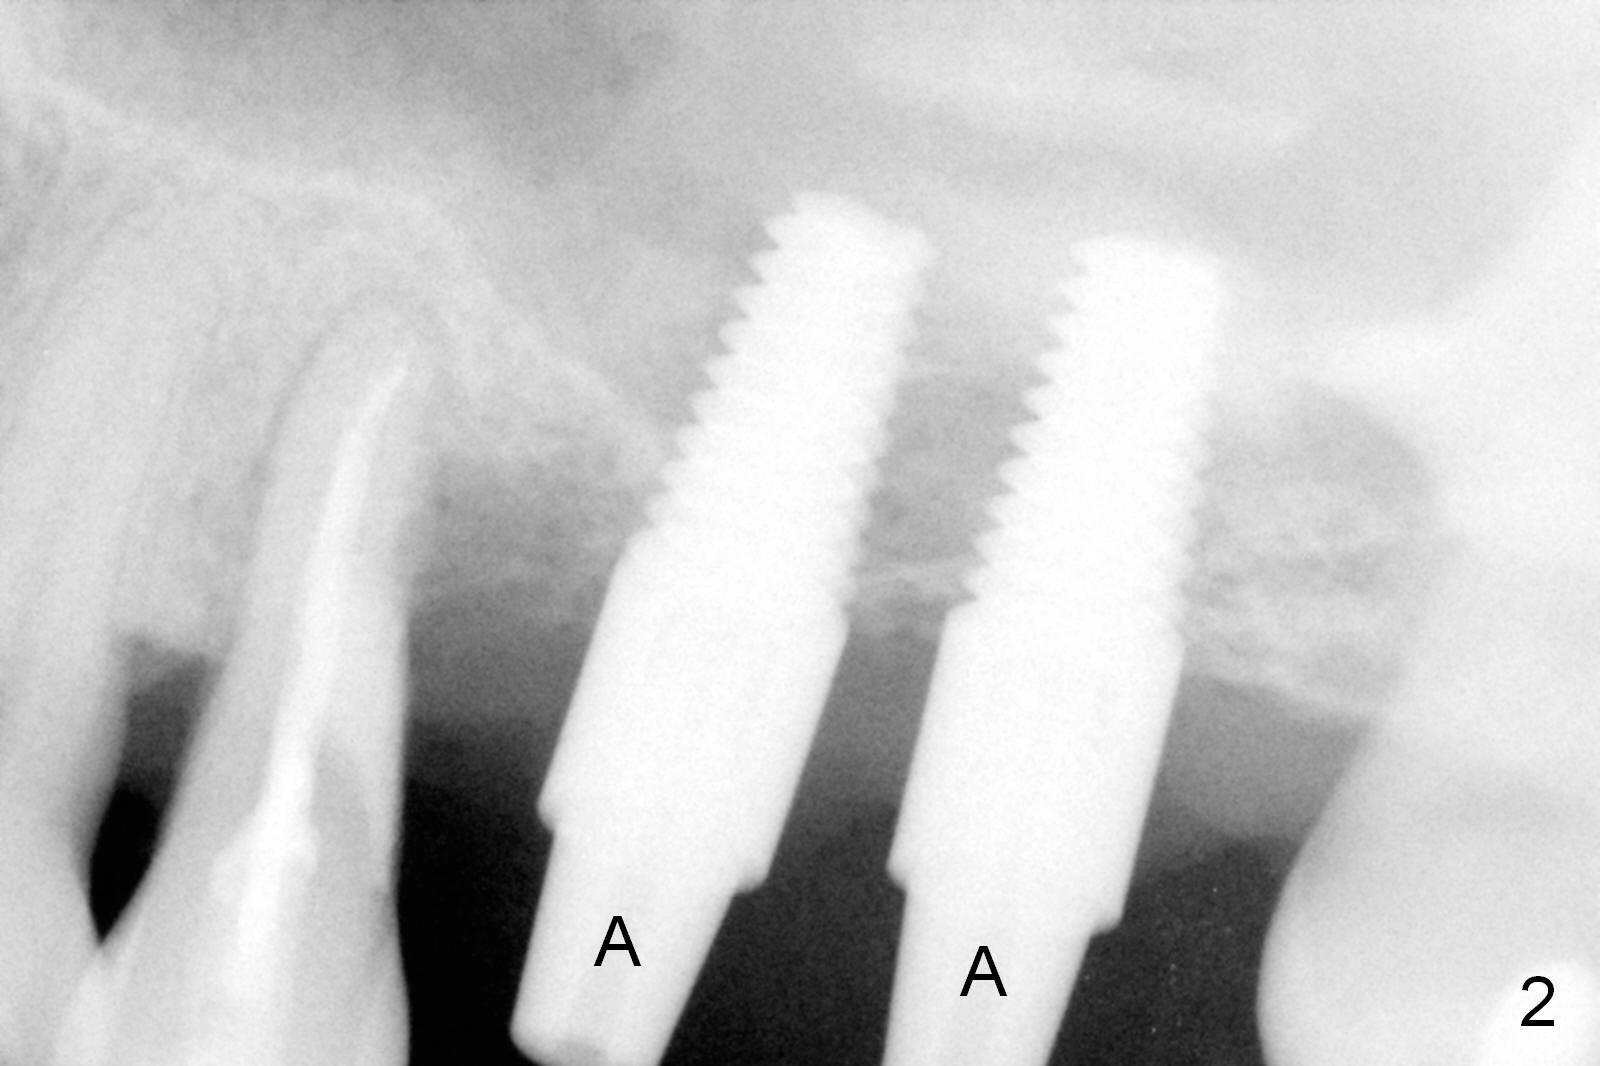

Mild to moderate hemorrhage is encountered as soon as incision is made for the lateral window. It is a concern prior to bone graft and implant placement. Hemorrhage appears to come from the sinus. Bleeding may wash away the graft. Therefore several pieces of Collagen Dressing are inserted into the sinus for hemostasis, followed by placement of Osteogen (Fig.1 *) and implant (5x14 mm, tissue-level). After placement of the 2nd implant, more Osteogen is placed buccal to the implants. Insertion torque is ~ 35 Ncm. Abutments (Fig. 2: 4x5 mm) are placed to hold perio dressing in place (no immediate provisional). In fact, the patient returns within 20 minutes postop because hemorrhage from the incision. Hemostasis is achieved with a few pieces of gauze in the buccal vestibule. Ice pack is recommended. By the evening, the patient reports minimal oozing. When perio dressing is lost 10 days postop, the wound opens (Fig.3). Later the wound heals. It appears that an immediate provisional provides the wound with temporary protection. The abutments without provisional is irritating to the soft tissue (the cheek in this instance). They have to be removed until the implants osteointegrate. PA taken 4 months postop shows the bone in the sinus surrounding the implants (Fig.4 *). The gingiva around the implants looks normal (Fig.5), although there is occasional and mild itching in the skin over the left sinus.